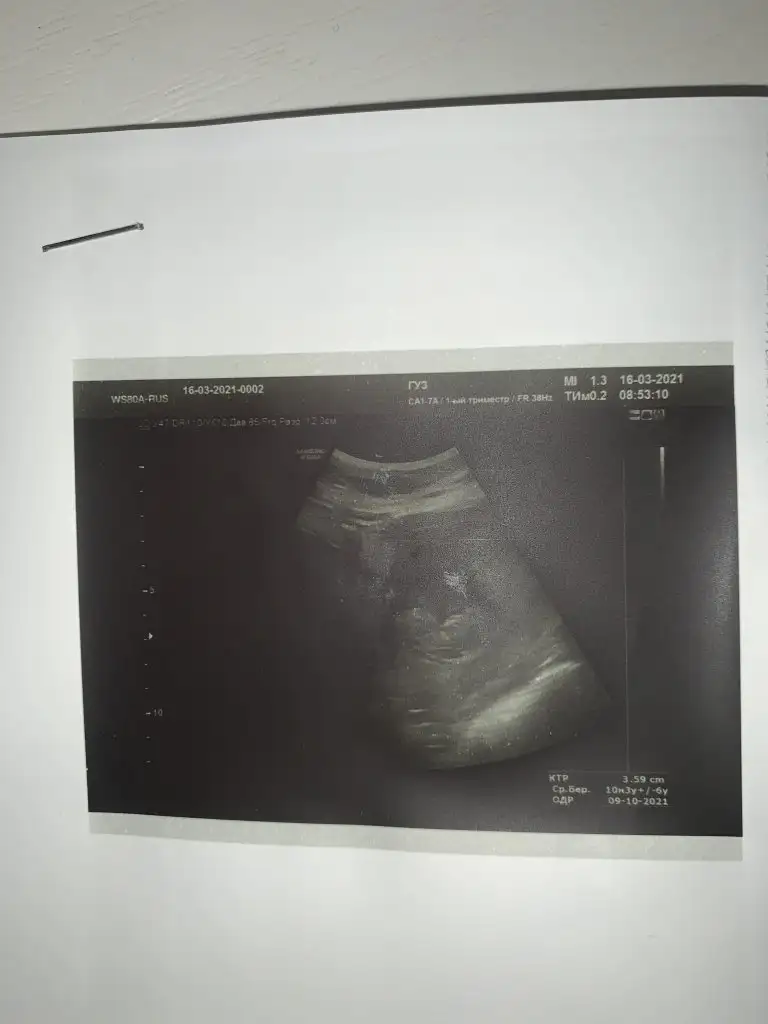

Ikra meyra Ikra meyra merhaba 11+4 deyim banada bir tahminde bulunabilir misiniz 🍀

Eklentiler

• 49B02C60-3426-4A3B-BE0C-A845F6668E72.webp

49B02C60-3426-4A3B-BE0C-A845F6668E72.webp

22,7 KB · Görüntüleme: 63